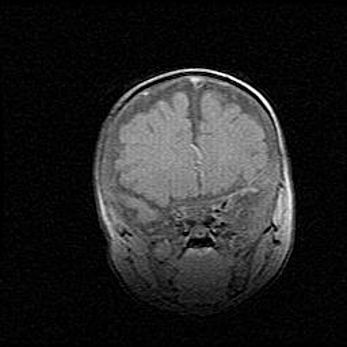

Неполная лизэнцефалия (пахигирия). Открытая гидроцефалия.

Возраст: 17 дней

Вес: 3110 г

Пол: мужской

Окружность головы: 33,5 см

Срок гестации: 35-36 недель

Лизэнцефалия—недоразвитие корковой пластинки и мозговых извилин в результате нарушения миграции нейронов коры. Поверхность мозговых полушарий гладкая. Микроскопически выявляется отсутствие нормальных слоев коры и скопление групп нейронов в подкорковом белом веществе.

Пахигирия—уменьшение числа вторичных извилин. В пораженном полушарии нервные клетки образуют толстый недифференцированный слой с неправильно расположенными нервными волокнами и группами гетеротопных клеток. Нервные клетки незрелые. Белое вещество истончено. При этом нередко аномально развит корково-спинномозговой путь.